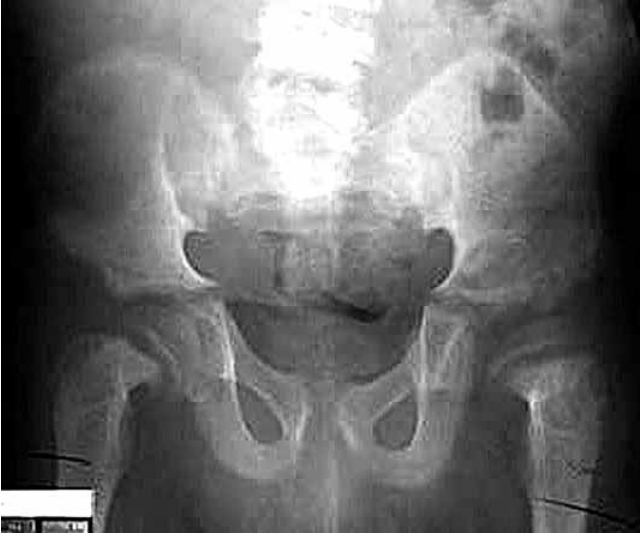

Adolescente de 14 anos é atendida com o relato de 2 semanas de evolução com dor no quadril e joelho direito. Não há comorbidades. Ao exame físico: regular estado geral; ela está acima do peso (95º percentil), com um índice de massa corporal de 26 kg/m2; nota-se diminuição da amplitude de movimento do quadril direito. Exames séricos são normais. A radiografia de quadril é mostrada a seguir.

(Arquivo pessoal; imagem usada com autorização)

O diagnóstico mais provável é: